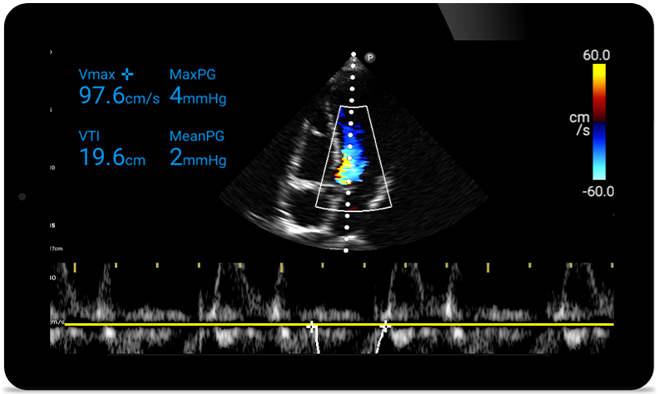

Act faster to protect their heart

When seconds count, portable ultrasound can make the difference. Lumify can provide the high-definition imagery you need whenever and wherever you need it.